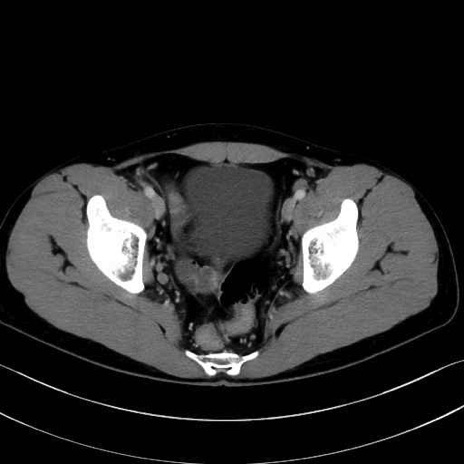

3. 殿部の筋肉(表層・中層・深層)

大殿筋 (Gluteus maximus)

中殿筋 (Gluteus medius)

小殿筋 (Gluteus minimus)

大腿筋膜張筋 (Tensor fasciae latae)

4. 深層外旋六筋(股関節の深部)

梨状筋 (Piriformis)

内閉鎖筋 (Obturator internus)

外閉鎖筋 (Obturator externus)

大腿方形筋 (Quadratus femoris)